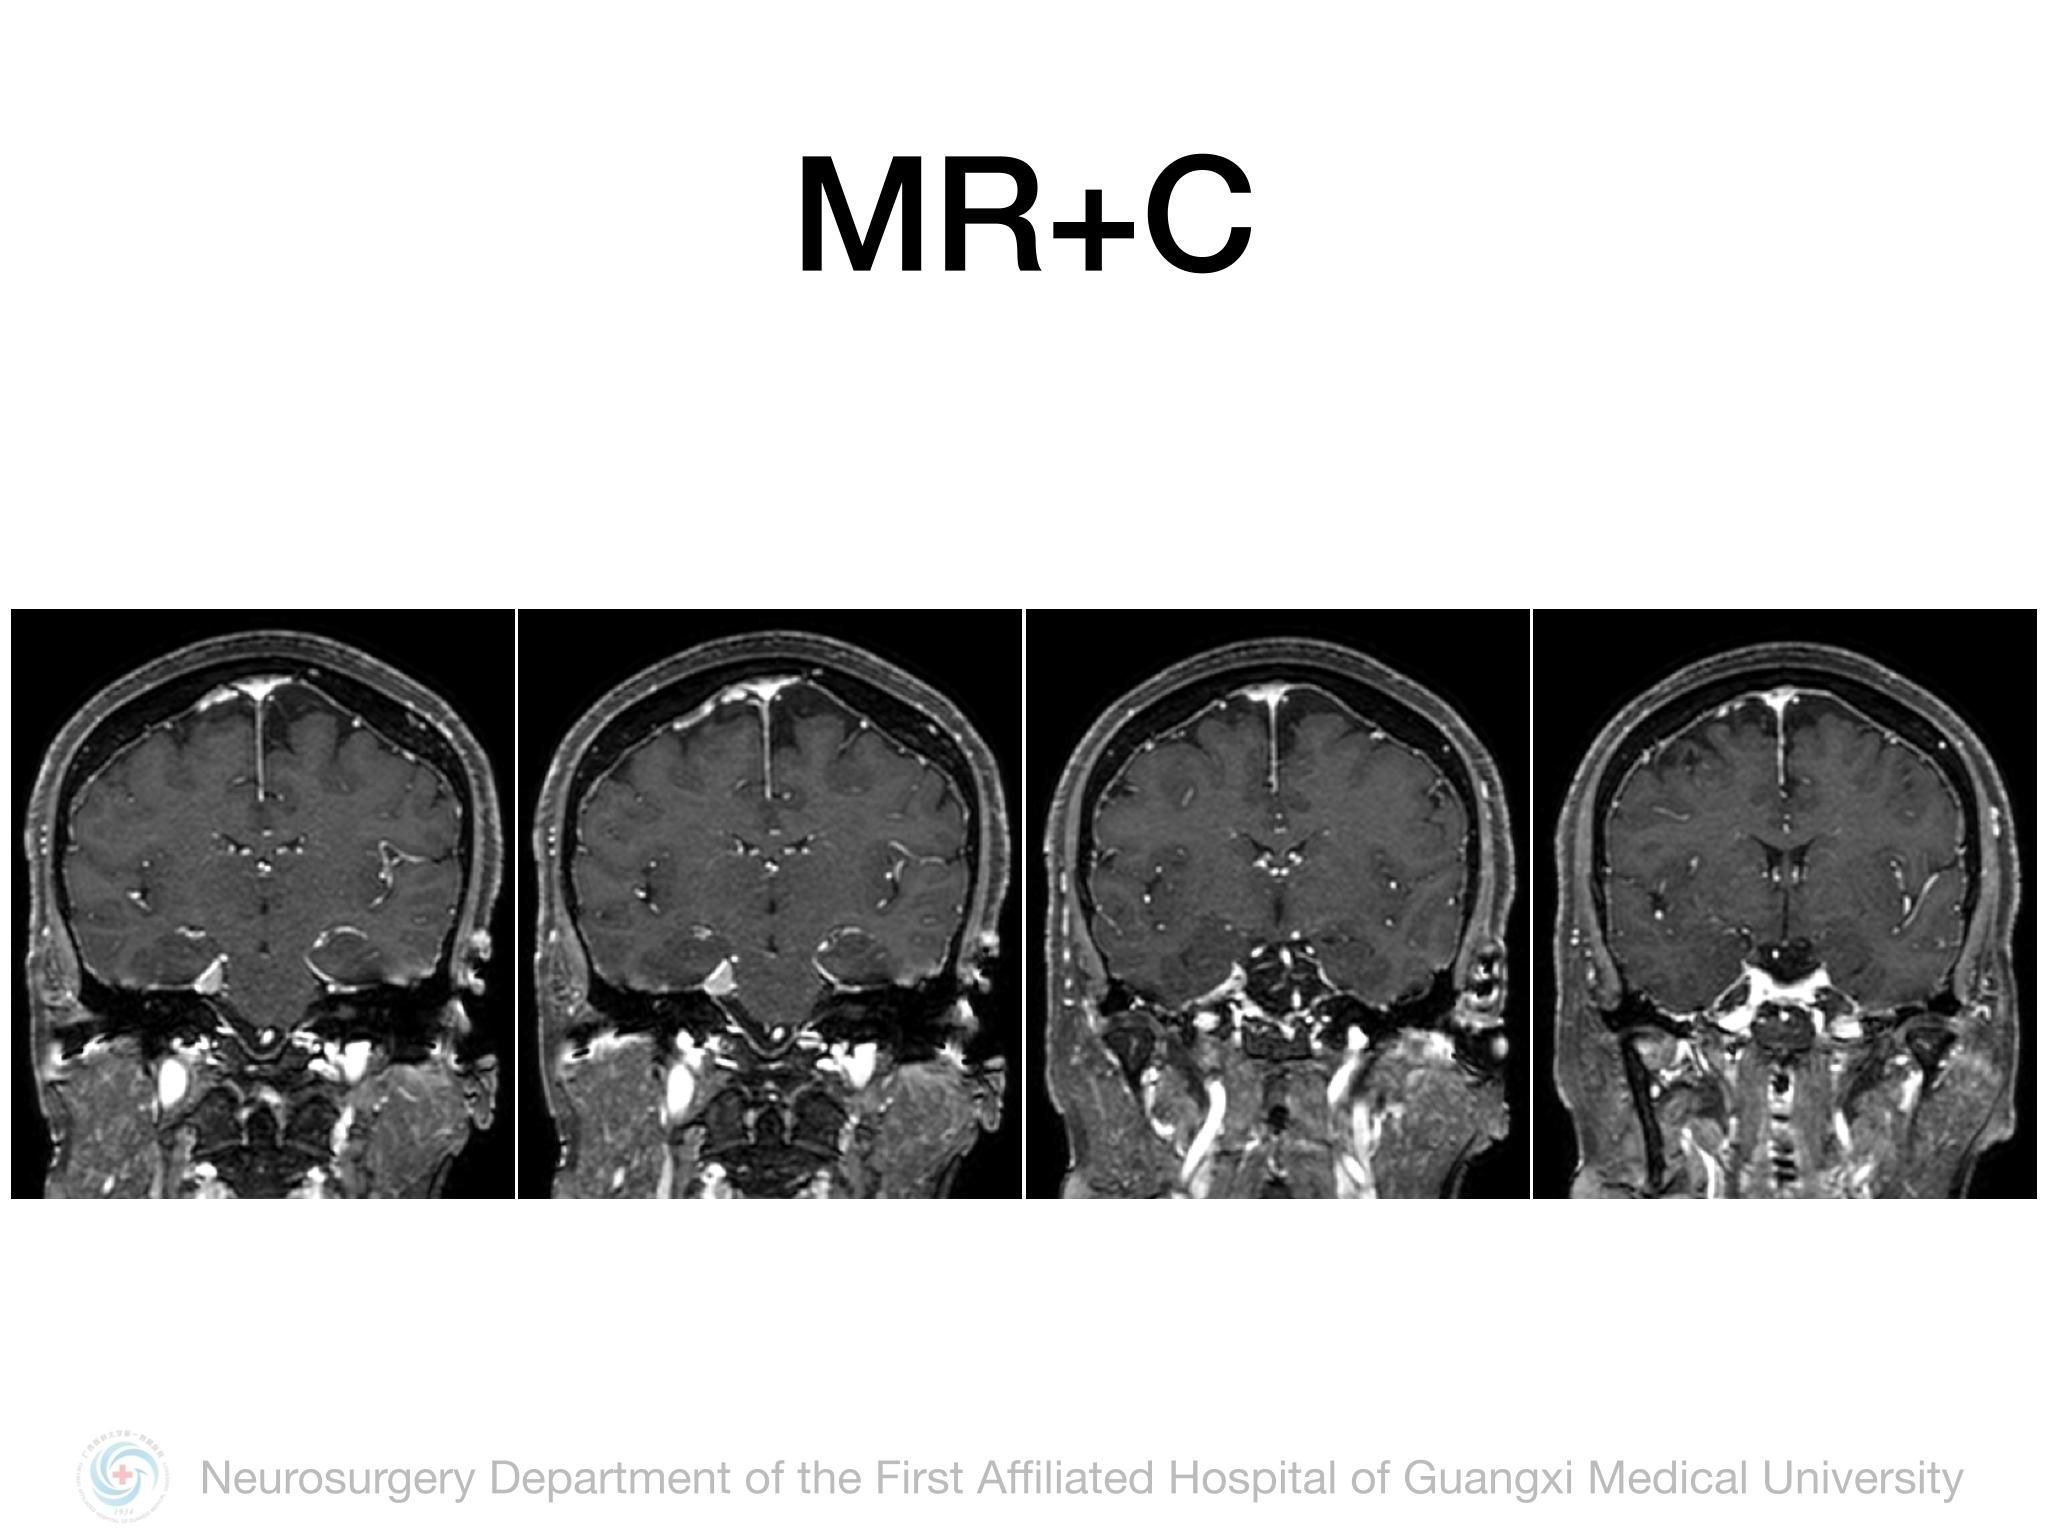

Meckel’s cave(MC)由多层硬膜围绕三叉神经半月结构成,通过三叉神经门与后颅窝蛛网膜下腔相通,起源于MC的脑膜瘤并不常见,文献报道约占所有颅内脑膜瘤的1%。Samii教授报道将MC脑膜瘤分4型,I型:局限于MC;II型:MC脑膜瘤向中颅窝扩展或海绵窦浸润;III型:MC脑膜瘤向CPA区扩展;IV型:MC脑膜瘤向中后颅窝均有扩展。本例属于I型,局限于MC,因此首选颞下经天幕入路,结扎岩上窦,显露部分岩尖,必要时硬膜下磨除岩尖。术中需注意颞叶及Labbe静脉壁保护,避免损伤岩静脉,尽可能全切肿瘤及基底。本例术中见肿瘤基底位于MC外侧壁及顶壁,主体位于MC,向后下推挤三叉神经,向后颅窝有部分延伸,但与脑干无黏连,向三叉神经内侧进入MC内侧空间,充分显露MC后将肿瘤及其基底全切,周围神经血管保护良好,术后无新发神经功能障碍,疗效满意。